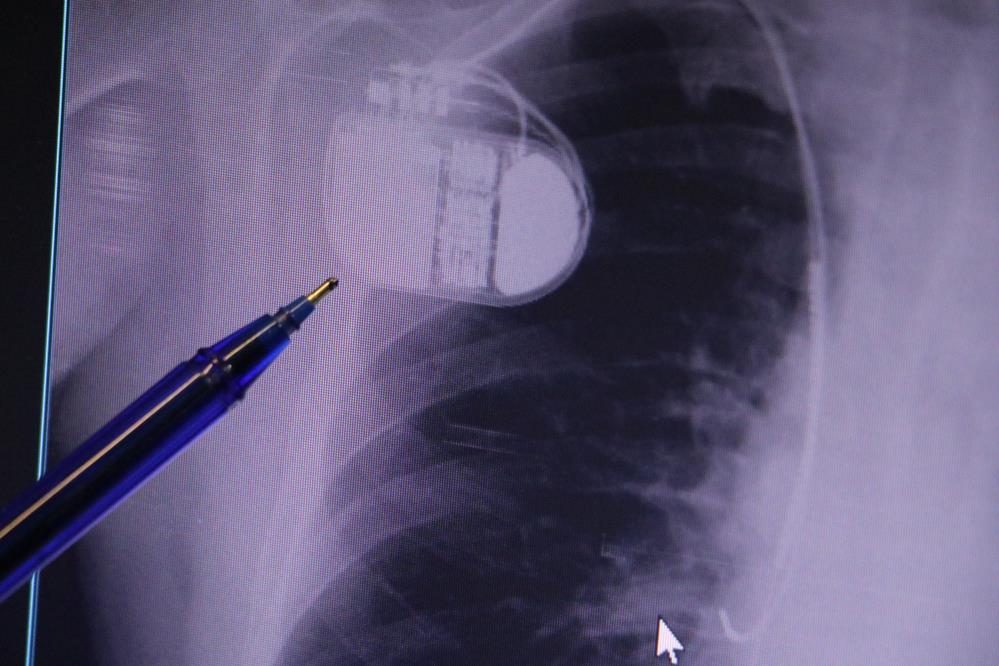

Sivas Medicana Hastanesi Kardiyoloji Uzmanı Dr. İsmail Erdoğu, kalp pili tedavisinin ani ölümleri önlemede büyük rol oynadığını belirterek, özellikle soğuk havalarda kalp pili kullanan hastaların dikkatli olması gerektiğini söyledi.

Dr. Erdoğu, kalp pilinin önemine dikkat çekerek, yeni nesil kalp pillerinin MR cihazlarına girmeye uygun olduğunu ancak tarama cihazlarından geçilmemesi gerektiğini belirtti. “Soğuk hava nedeniyle oluşan titremeler, kalp pilinin kalbin durduğunu sanmasına ve yanlış şoklamaya yol açabilir. Bu nedenle hastalarımızın bu dönemlerde daha dikkatli olmalarını öneriyoruz” dedi.

Kalp krizleri sonrası kalpte oluşan hasarın uzun vadede ritim bozuklukları ve ani ölümlere yol açabileceğini söyleyen Erdoğu, “Kalp pilleri, uygun hastalarda ani ölümleri engelliyor. İnsanlar bir şokla hayata tutunurken, pil olmasaydı öleceğini düşündüğümüz birçok hastamız var. Soğuk havalarda vücutta oluşan titremeler, kalp pilinin hafızasını karıştırıp gereksiz şoklamaya yol açabilir. Bu nedenle bu dönemde temkinli olunmalı” diye konuştu.